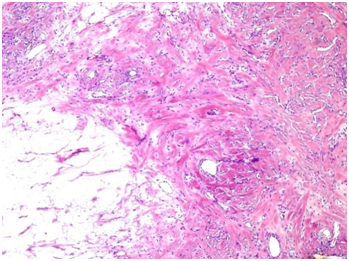

Based on the above described findings, the lack of guidelines and misleading clinical symptoms, our tumor board decided to offer the patient a laparotomy with left salpingo-oophorectomy. We performed an infraumbilical incision of the abdomen. The right ovary and uterus were macroscopically normal. Gross examination showed a marked left ovarian enlargement with smooth white external surface. The uncertainty of malignant potential due to the size of the lesion was the reason to perform a salpingo–oophorectomy. En bloc resection of the tumor was performed. One litre of clear fluid emerged after the incision of the surface. Microscopic examination revealed marked oedema of ovarian stroma with its architecture preserved. Normal germinal follicles were present without signs of necrosis but abundant cystic lesions were seen on the upper surface of the ovary (Figure 2) (Figure 3).

Figure 3 Central region of fibrosis with vascular and lymphatic channels. Cortex with oedematous infiltration on the left.